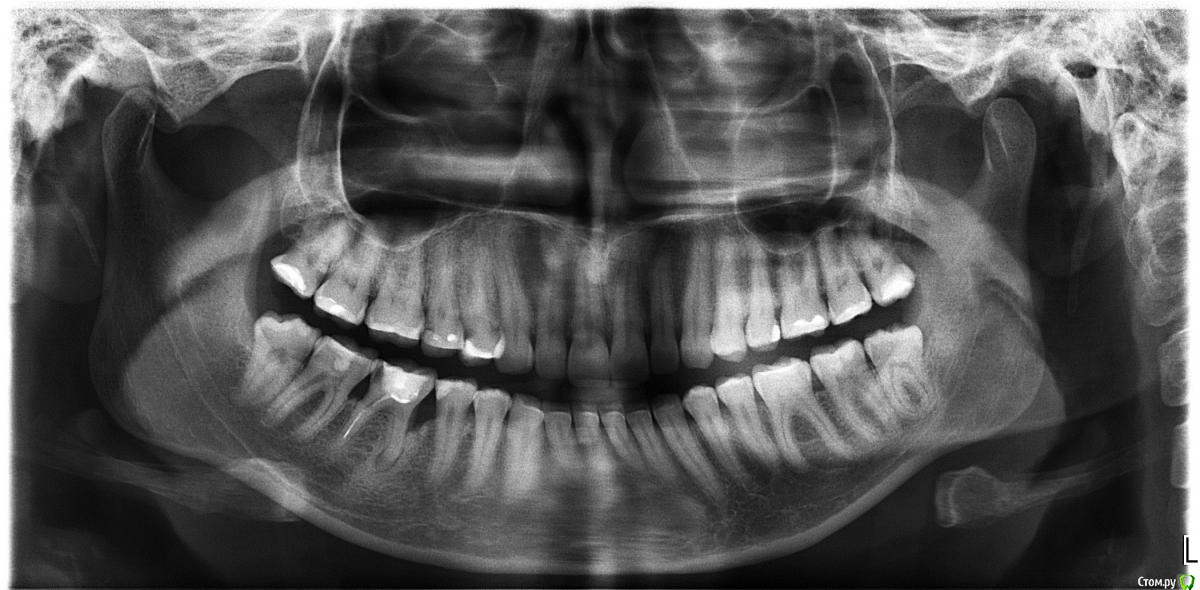

Natalya1984 Опубликовано 11 октября, 2016 Поделиться Опубликовано 11 октября, 2016 Добрый день.В 2007 году был залечен зуб, при удалении нерва 1 канал запломбировали плохо, во втором оставили инструмент, но об этом я узнала совсем недавно. В 2003 на этом же здесне под этим зубом была операция (подсаживали костную ткань). Сегодняшнее состояние зуба на снимке. Можно ли перелечить зуб или оставить как есть, пока сам не выпадет?Заранее спасибо за ответы. Ссылка на комментарий

St. Опубликовано 12 октября, 2016 Поделиться Опубликовано 12 октября, 2016 Вариантов у Вас три.1. Попробовать перелечить. Сложно, дорого, без гарантии, но в случае успеха получится сохранить свой родной зуб. И если это получится - это очень хорошо.2. Удалить и поставить имплант сейчас. Еще дороже, прогнозируемее, но вместо родного зуба будет титановый корень. 3. Ничего не делать. Кость будет разрушаться дальше, в любое время теоретически он может начать беспокоить. И вопрос с ним станет все равно. Ссылка на комментарий

DmitrySH Опубликовано 12 октября, 2016 Поделиться Опубликовано 12 октября, 2016 Вариантов у Вас три.1. Попробовать перелечить. Сложно, дорого, без гарантии, но в случае успеха получится сохранить свой родной зуб. И если это получится - это очень хорошо. если с периодонтом можно решить вопросы, то с пародонтом достаточно проблемно. В случае ремиссии, скорее всего, останется пародонтальный карман. Ссылка на комментарий

St. Опубликовано 13 октября, 2016 Поделиться Опубликовано 13 октября, 2016 Здесь ( как минимум мне) не ясна причина кармана в обл.45 46, учитывая относительное благополучие в других участках Ссылка на комментарий

red_butler Опубликовано 14 октября, 2016 Поделиться Опубликовано 14 октября, 2016 Здесь ( как минимум мне) не ясна причина кармана в обл.45 46, учитывая относительное благополучие в других участкахтам вроде нет контактного пункта и пломба на пятерке мягко говоря странная Ссылка на комментарий

DmitrySH Опубликовано 14 октября, 2016 Поделиться Опубликовано 14 октября, 2016 там вроде нет контактного пункта и пломба на пятерке мягко говоря странная это точно, но здесь что-то еще. Может зубочистка + травматический узел. Дистально от 46 тоже кость ушла Ссылка на комментарий